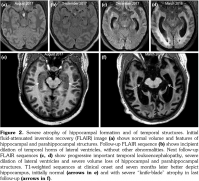

Initial brain MRI, using a standard protocol, was normal (Figures 1a and 2a). Due to rapid deterioration of the neurological status, a follow- up MRI was performed three weeks later (Figures 1b and 2b), including gadolinium administration and angiographic sequences. A mild periventricular nonspecific leukoencephalopathy and an incipient dilation of the supratentorial ventricles were observed. No abnormal contrast- enhancement was present. MRI angiography and venography showed permeability of the vessels. The patient continued to deteriorate, in a span of several weeks, despite initiating high-dose intravenous methylprednisolone. The clinical suspicion of vasculitis was raised and a third MRI was performed, at 3.5 months from the onset, with a specific protocol including vessel-wall three-dimensional (3D)-high-resolution pre- and post-contrast black-blood sequences. This MRI showed severe progression of the leukoencephalopathy, and associated atrophy with marked dilation of the ventricles and the subarachnoid spaces (Figures 1c and 2c). High-resolution vessel-wall sequences showed multiple arterial segments with concentric contrast enhancement of the wall, of proximal and distal distribution (Figure 3), compatible with vasculitis. A treatment with high-dose intravenous cyclophosphamide was started. Clinical follow- up revealed a progressive improvement of the drowsiness with eventually stabilized neurological status, but the cognitive deficit was already extremely impaired. The fourth MRI exam, at seven months from the clinical onset, showed even more severe atrophy (Figures 1d and 2d). A comparative of the hippocampal formation, crucial for the memory circuit, showed normal features on the first MRI (Figure 2e) and marked “knife blade” atrophy on the last study (Figure 2f). Concomitant diseases, including cerebrovascular and cardiovascular events, were ruled out.